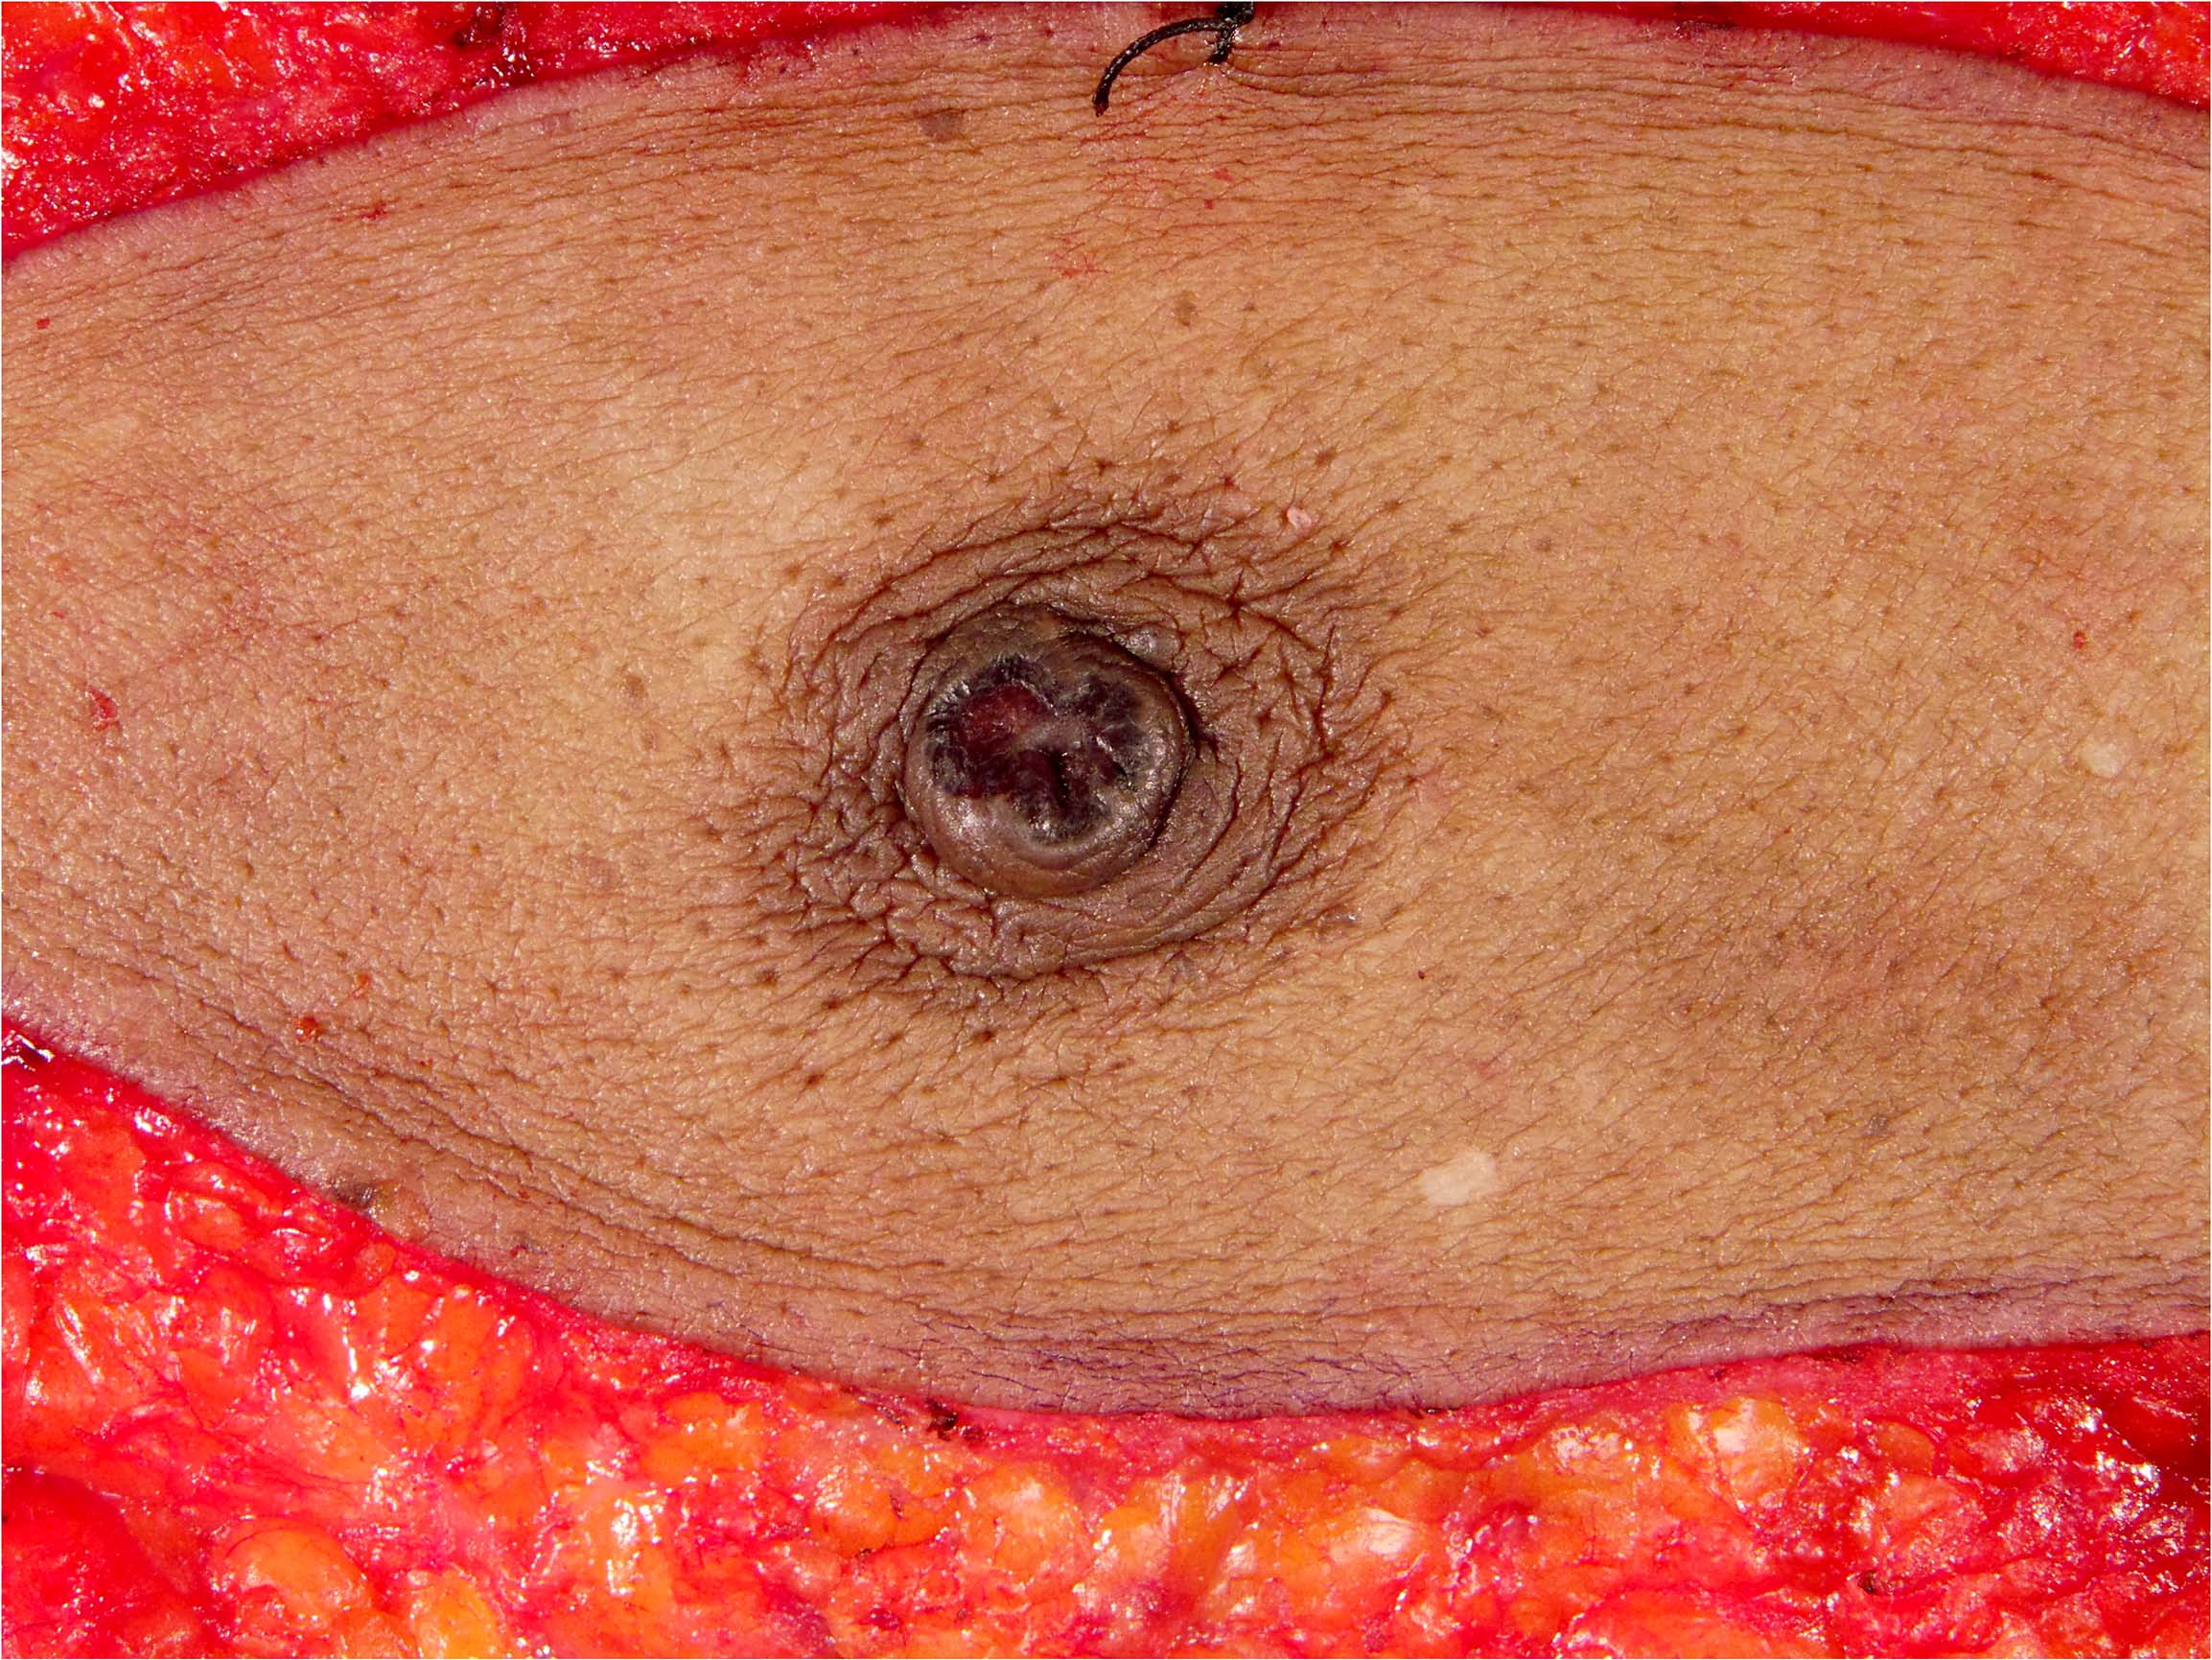

Clinical images

- Nipple areolar complex with red-pink crusting lesion, discoloration, thickening, ulceration, exudate, nipple retraction, etc.

- Typically well demarcated; epidermal involvement usually does not extend beyond the grossly evident lesion (Cancer Treat Rev 2001;27:9)

- Scaling crust may be removed by skin preparation prior to surgery

Gross images